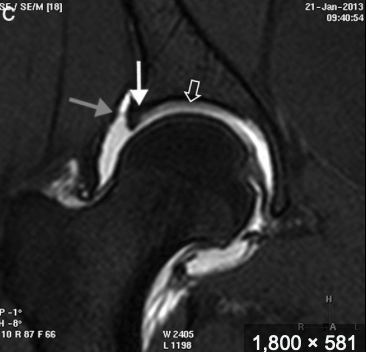

RM pinzamienro femoroacetabular

Edema óseo hiperintenso

Pinzamiento leve

Lesión del labrum